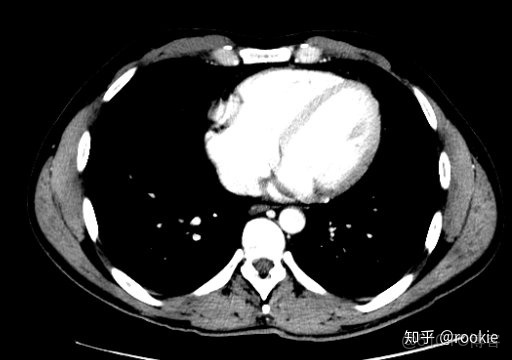

CTA窗口窗口設置: (W:600,L:170)或(W:650,L:225)優點: 在評估CT血管造影研究(或在血管中具有明顯對比的CT掃描的任何階段)時,此設置可用於嘗試清晰地觀察血管病變。它在提供目標血管信號的同時具有良好的平衡,而無需血管內的亮度過高會沖洗腔內病變。

CLAHE算法增強局部對比度的X光圖像增強效果對比_ico_14

此窗口用於在感興趣的血管中有相當大的對比度的情況下(例如CT血管造影)。